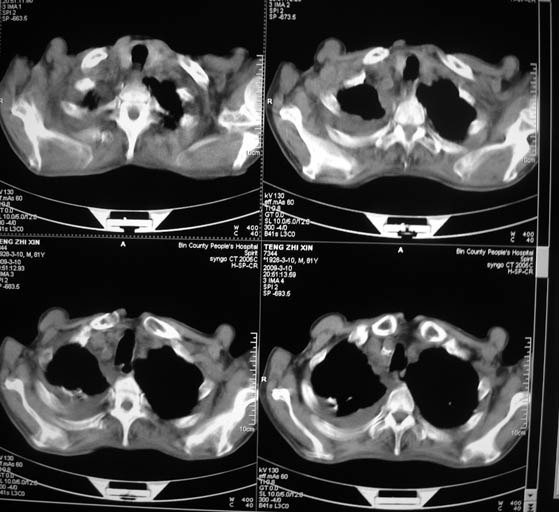

标题: CT18642:男,81岁,发热待查。

男,81岁,发热待查,右侧是占位还是膈疝?

很明显的排除膈疝。考虑右肺中央型肺癌,建议增强。胸腔恶性胸水。

考虑右侧中央型肺癌、双侧胸水,必要时做个增强看看